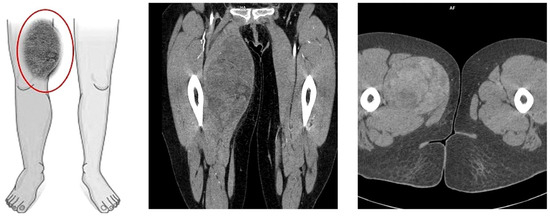

The histopathological blocks from the operation were then re-analyzed in Warsaw. A FISH DDIT3 test and an additional IHC test were ordered. In the assessment of rearrangements within the DDIT3 gene, 95% of the examined cells were confirmed to be neoplastic. Tumors having round cell components higher than 5% of all tumor volumes were considered high grade (9% in this case). The below image (Figure 4) indicates rearrangements within the DDIT3 gene (12q13). In addition, the IHC confirmed SOX 11 (+). The FISH test results confirmed the diagnosis of myxoid liposarcoma. Due to the focally increased cellularity of the lesion, the diagnosis was changed to high-grade MLPS FNCLCC (Federation Nationale de Centros de Lutte Contre le Cancer) Grade 2 (G2) (Figure 4). In a chest CT scan, MRI of both lower limbs, abdominal—pelvic CT, and MRI of the whole body, there were no signs of metastases (M0 N0). The treatment plan changed during the preparation of this article. The first plan was to prepare the patient for a specific expert orthopedic oncology operation; however, after seeing the NGS and FISH results and changing the diagnosis to high-grade myxoid liposarcoma, an oncological committee review (tumor board review) was performed. This tumor board always includes a surgeon specializing in the relevant area, a clinical oncologist, a geneticist, a radiation therapist, and a chemotherapist. The decision was to perform neoadjuvant radiotherapy and chemotherapy before the operation (Figure 3). The patient gave written consent to publish the description of her case.

Figure 4.

Microscopic image from the Department of Soft Tissue/Bone Sarcoma and Melanoma Maria Skłodowska-Curie Memorial Cancer Center in Warsaw. High-grade MLPS FNCLCC (Federation Nationale de Centros de Lutte Contre le Cancer) Grade 2 (G2). (A) H&E (hematoxylin and eosin steins) 20× (B) H&E 40×.